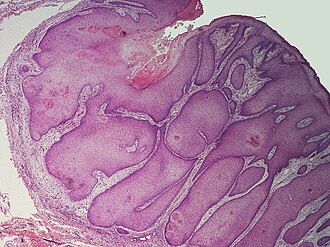

| Possibly a pilar sheath acanthoma. H&E stain. | |

| LM | cystic cavity with branching - contains keratineous material, usually extends from surface to deep cutis, cyst lining consists of a thickened squamous epithelium |

- Cystic cavity with branching:[3]

- Contains keratineous material.

- Usually extends from surface to deep cutis - like a hair shaft.

- Cyst lining consists of a thickened squamous epithelium (acanthosis).

- +/-Mitoses.